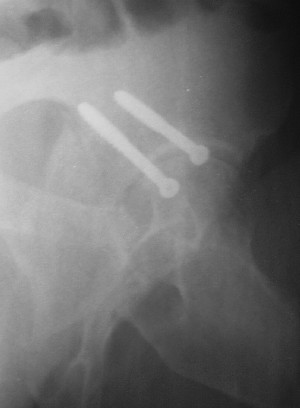

Контрольный снимок перед разрешением нагрузки прямой 13/10/03

Больной 18 мая 2003 года в автоаварии получил перелом левой вертлужной впадины, вывих бедра. Госпитализирован в один из стационаров области.Вывих вправлен. В последствии бедро вывихивалось еще дважды. На консультацию был представлен снимок от 19.05.03г., больной переведен к нам 3.06.03г. Снимок при поступлении - перелом впадины, задне-верхний вывих бедра. 05.06.2003 г. выполнено открытое вправление вывиха левого бедра и остеосинтез стенки вертлужной впадины двумя винтами. Послеоперационный период без осложнений. Объем движений в левом тазобедренном суставе восстановился полностью. Выписан на амбулаторное лечение в удовлетворительном состоянии с рекомендациями 3 месяца ходить на костылях без нагрузки на оперированную конечность. На контрольных рентгенограммах левого тазобедренного сустава 13.10.2003 г. - признаки консолидации перелома; плотность, форма головки и состояние суставных поверхностей удовлетворительные. Разрешена дозированная осевая нагрузка, на конечность с использованием дополнительной опоры. 19.12.2003 г. больной обратился с жалобами на боли в левом тазобедренном суставе. На рентгенограммах левого тазобедренного сустава 19.12.2003 г., 20.02.04г. - асептичекий некроз головки бедра. 5.04.04г. - эндопротез. Сейчас ходит без трости, не хромает. Особенность эндопротезирования - при удалении винтов прослежена линия перелома заднего края впадины и предложено установить чашку несколько меньшего диаметра, чтобы она была покрыта несломанной частью.